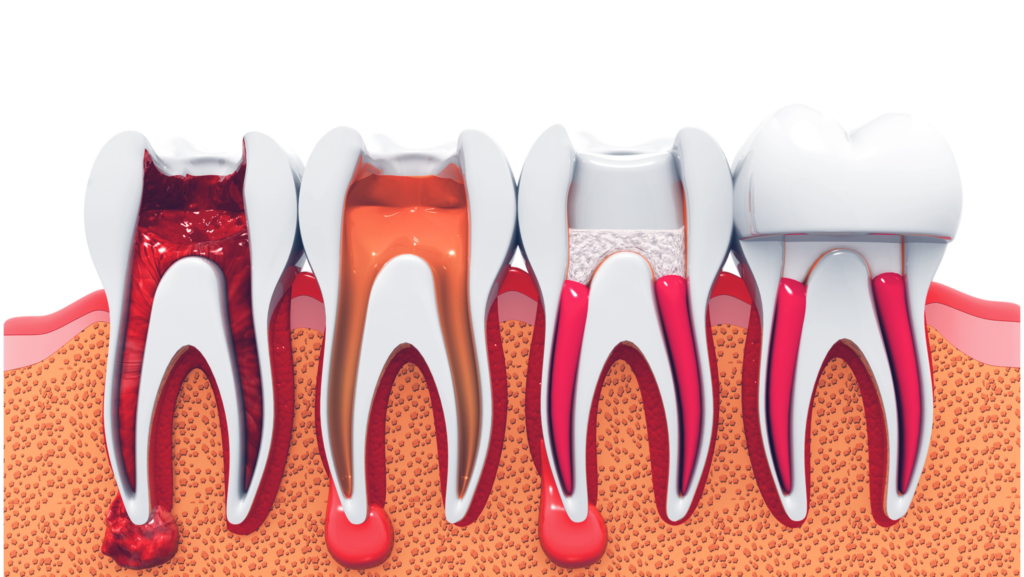

Root Canal Treatment

Root canal treatment is performed when the inner pulp of a tooth becomes infected or inflamed due to deep decay or trauma. The procedure involves removing the infected tissue, cleaning and disinfecting the canals, and sealing them to prevent reinfection. This treatment eliminates pain, preserves the natural tooth, and prevents the need for extraction.